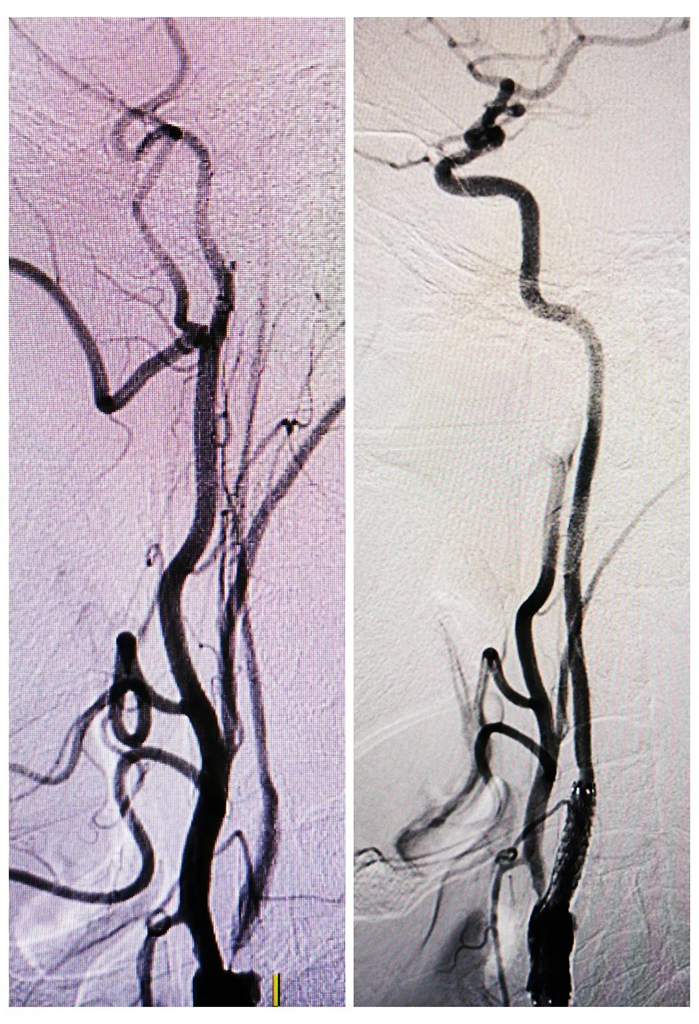

左:DSA示左侧颈内动脉起始部次全闭塞、

以远段管腔显影、细小,

与MRI血管壁成像所见相符

右:DSA示左侧颈内动脉起始部支架置入,

血流恢复